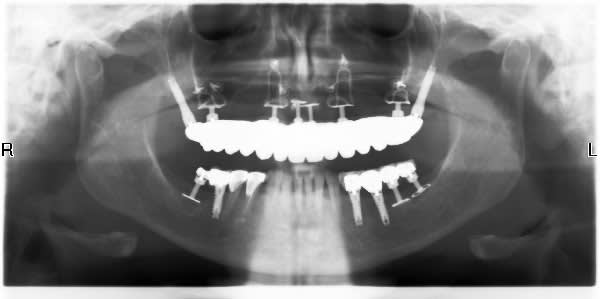

Sinon là tu as un joli mélange d'implants lames et de clous à la Chercheve qui doivent remonter à 50 ans environ.

Une des radios montre une prothèse avec un implant "racine", je crains que cela ne pose des problèmes de mobilité relative entre les deux systèmes.

L'un étant complètement fixe, l'autre, le juxta-osseux, devant avoir une certaine souplesse.